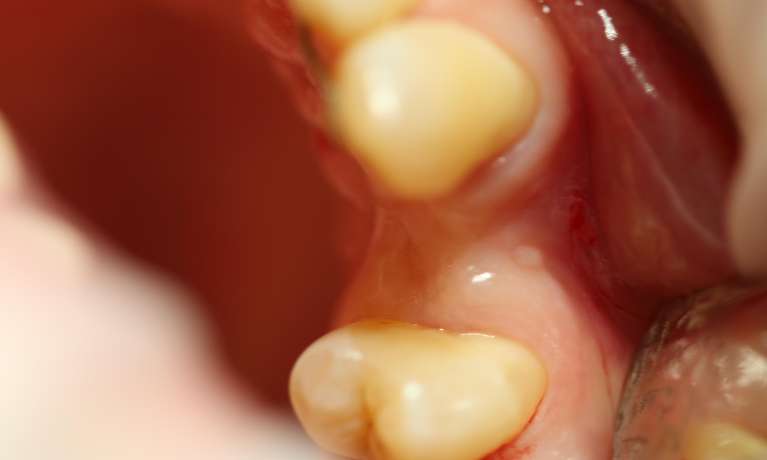

This case showcases the successful outcome of a gum graft procedure performed around an existing dental implant. Initially, the patient experienced gum recession around their implant, which can sometimes expose the implant's margin or simply lead to an uneven gum line.